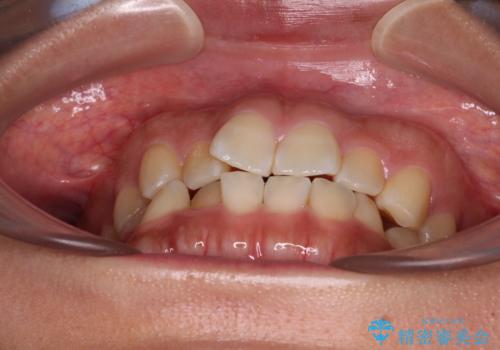

- 前歯のデコボコと口元の突出感を気にして来院された患者様です。

非抜歯矯正ではデコボコを解消することでより口元が突出してしまうため、上下左右の小臼歯4本の抜歯を行い、ワイヤー装置による矯正治療を行うこととしました。